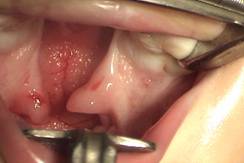

6. Al deslizar el paladar hacia atrás hay un riesgo alto de fístulas en la parte anterior del paladar las cuales son muy difíciles de corregir en el futuro, de hecho ese es el mayor inconveniente de la técnica. Para evitar esas fístulas es fundamental un cierre cuidadoso con colgajos de vomer en la parte más anterior (Fig. 10 y 11).

Figuras 10 y 11: Disección del colgajo de vomer y su sutura en la porción más anterior justo detrás del alvéolo.